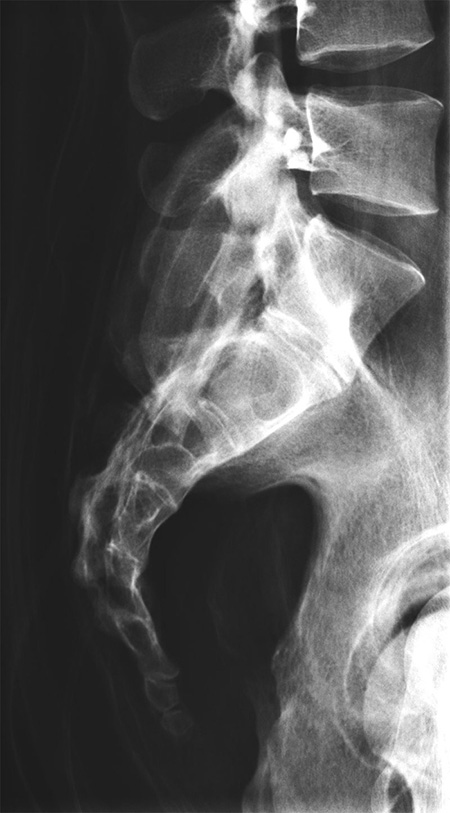

德國(guó)Erler Zimmer 7200天然骨骼全身模體,EZ 7200全身模體包含一個(gè)真實(shí)的人體骨骼,可以像患者一樣拍攝真正的X射線圖像。使用真實(shí)的骨架可以提供最小的導(dǎo)向結(jié)構(gòu),這對(duì)于塑料骨架來說是不可能的。

7、滿足任意部分進(jìn)行X線/CT掃描,成像效果與真實(shí)人體一致,影像片中能正常分辨出骨齡。

The phantom contains a real human skeleton, which allows taking real X-ray images like in a patient. Using a real skeleton provides even smallest guiding structures which is impossible with a plastic skeleton.